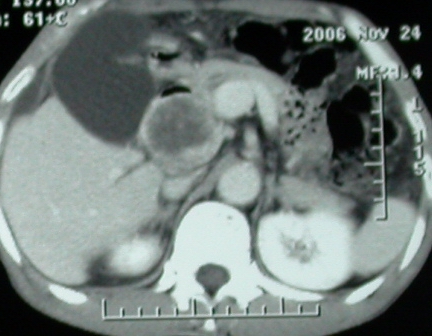

增强ct所见

ct表现:1,胰腺钩突后方肿块,不均强化,中心密度低,钩突及门静脉前移。2:肝右后叶不均强化灶,突出肝表面,3:胆囊明显增大,肝内胆管及肝总管内积气。4:腹腔内少量积液。

肝脏尾状叶肝癌(沿肝十二指肠韧带向下韧带内生长,门腔间隙外压增大),大结节性肝硬化,胆囊积脓,胆道感染。术中见肝外胆道2cm直径,肿瘤向前压迫胆管至扁平状态。